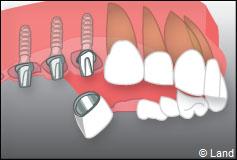

Exemple d’un implant unitaire pour remplacer une dent antérieure manquante.

Exemple de 3 dents manquantes remplacées par 3 couronnes sur implants.

Pose des piliers prothétiques et des 3 couronnes scellées.